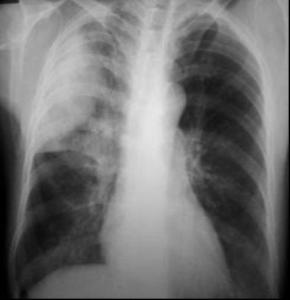

♥肺炎链球菌性肺炎